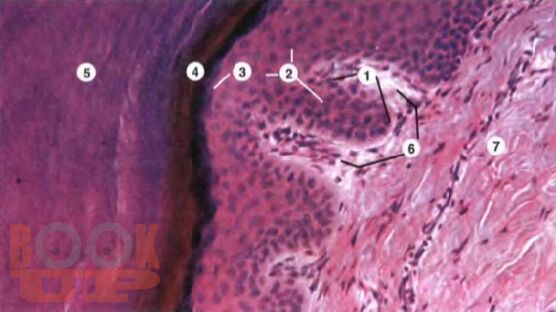

В монографии представлены результаты оригинальных исследований, посвященных судебно-медицинской оценке резаных и рубленых повреждений "барьерных" тканей волосистой части головы, с целью установления их морфологических особенностей в зависимости от действия режущих и рубящих объектов, имеющих лезвия различной остроты. Авторами на основании экспериментальных исследований, подтвержденных практическими наблюдениями установлено, что объективная экспертная оценка морфологических особенностей повреждений "барьерных" тканей волосистой части головы от различной остроты лезвия возможно только с учетом их анатомо-морфологических свойств. Разработан алгоритм экспертной оценки повреждений "барьерных" тканей волосистой части головы, позволяющий объективно установить механизм их образования и выраженность остроты лезвия.